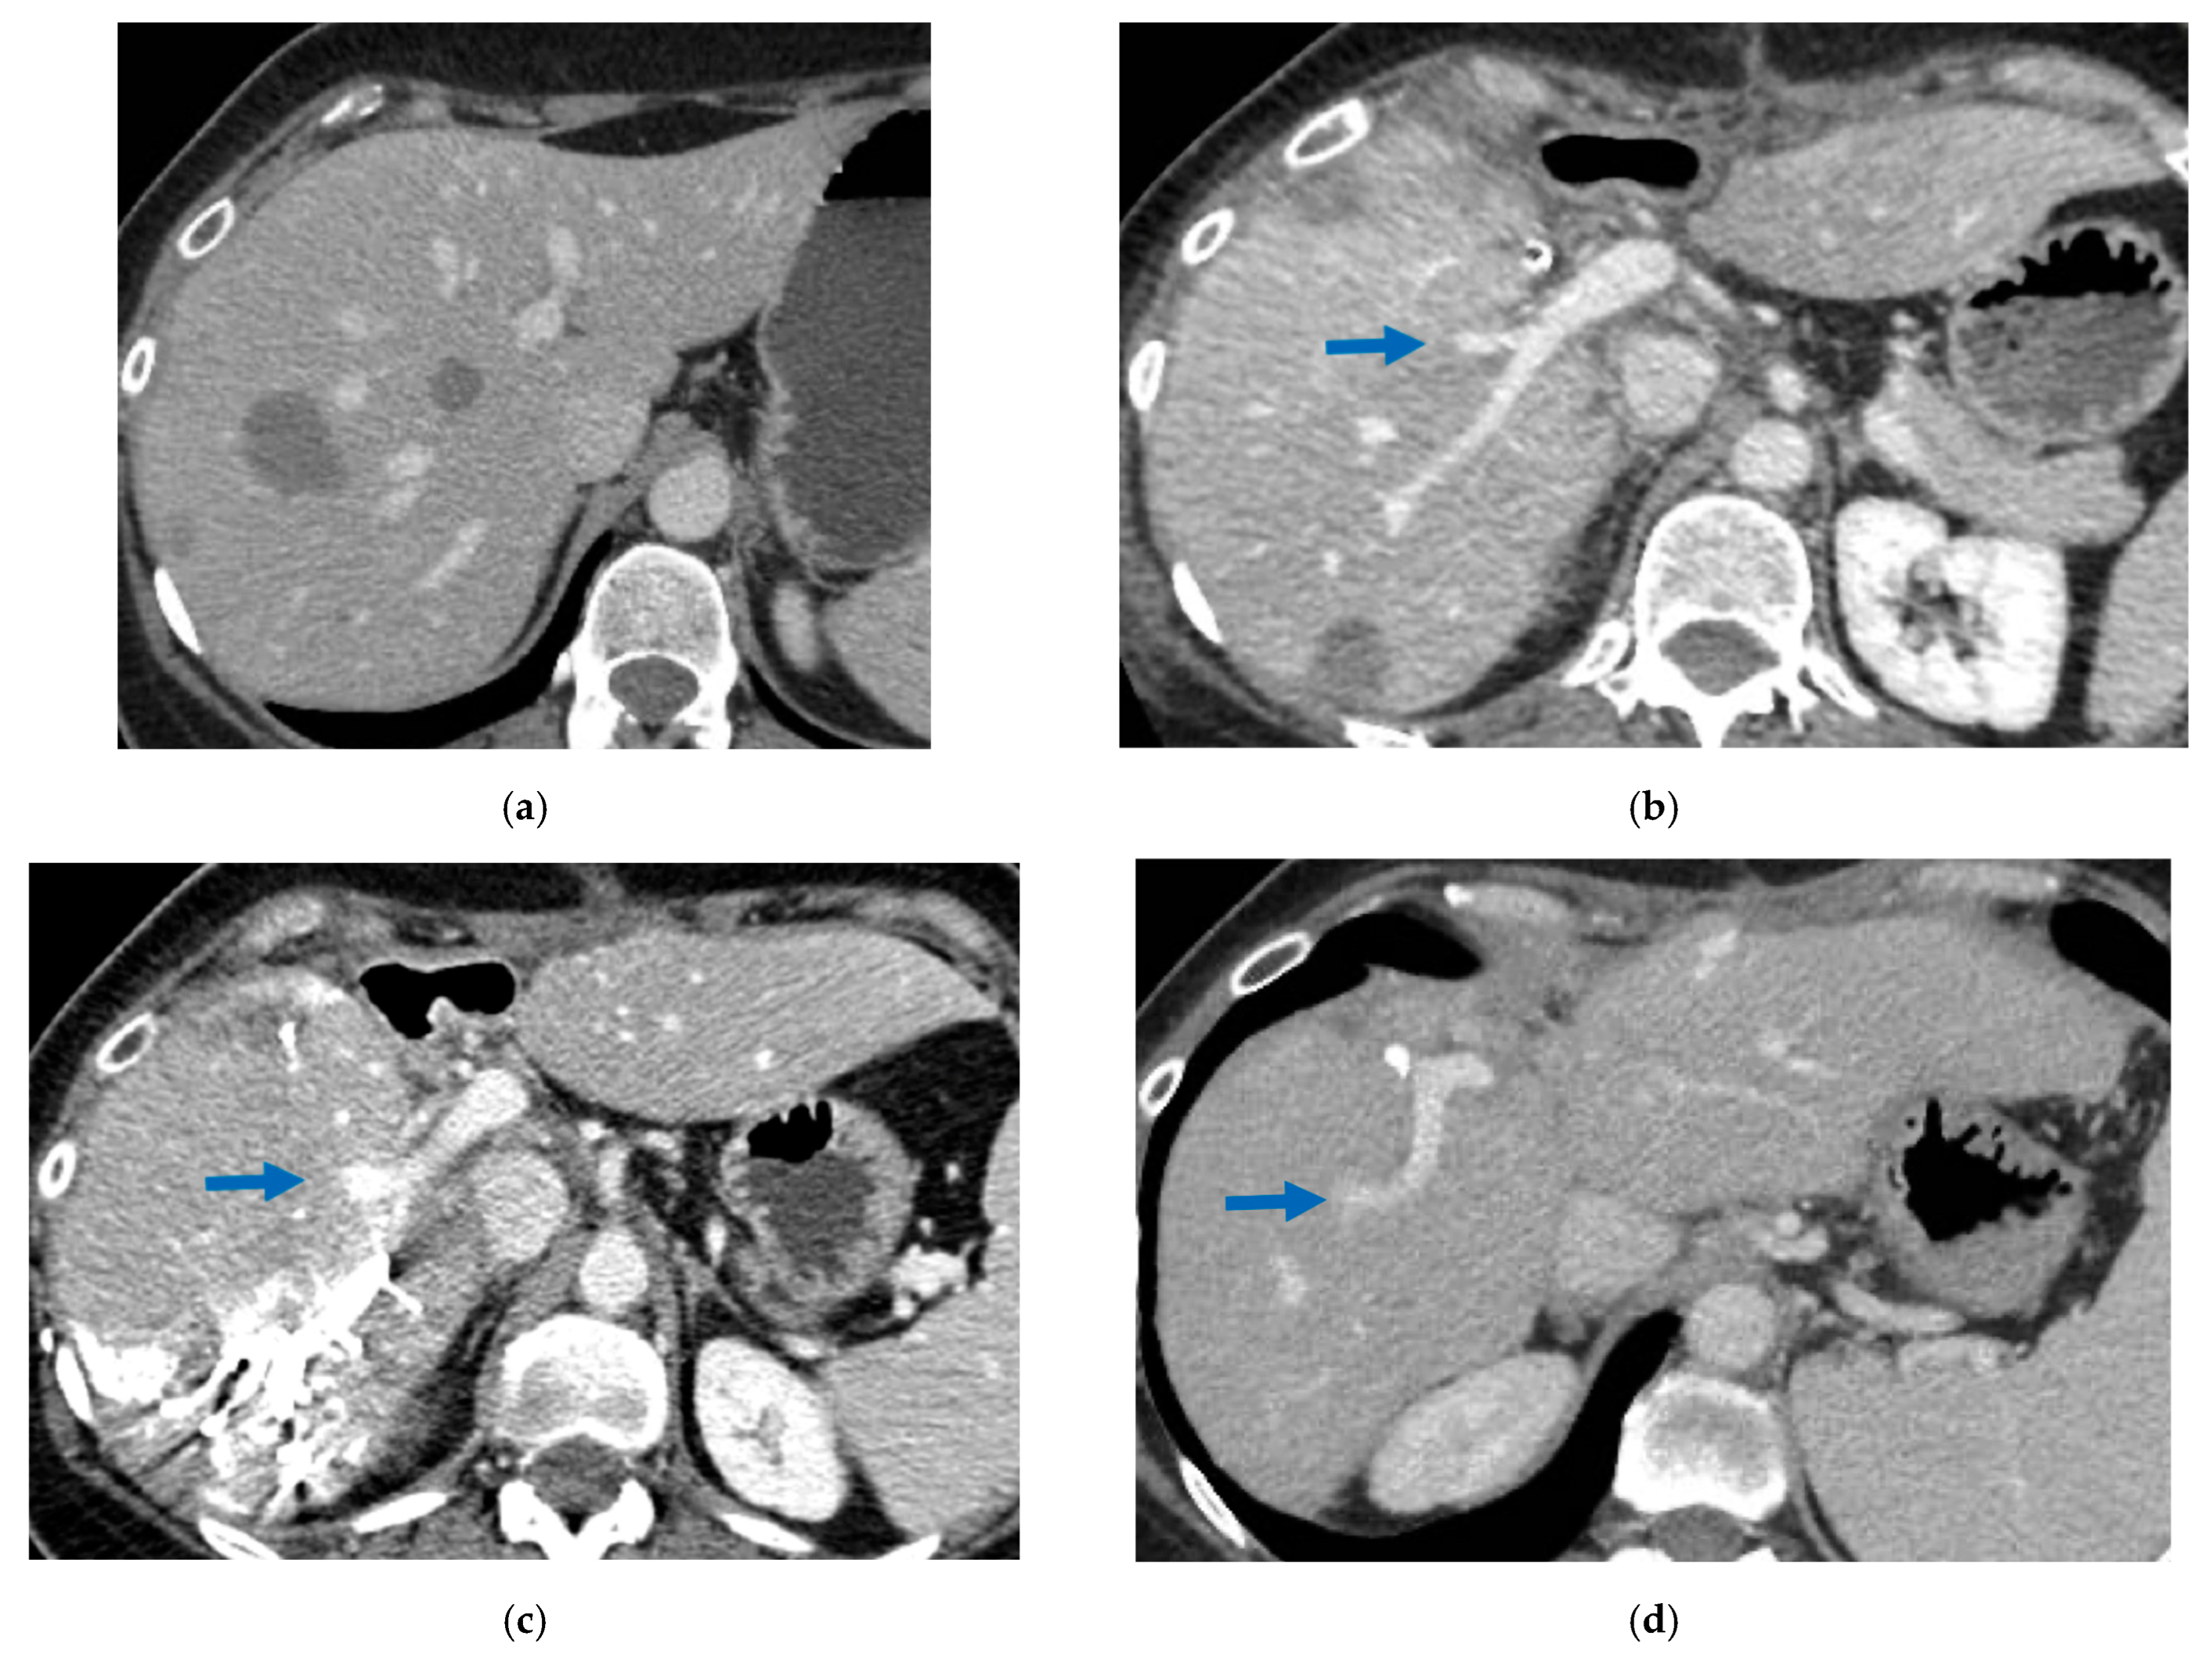

Figure 6. CT Images of PS-TSH with SS-PVE performed to treat 35 bilateral CRLMs. (a) Partial response after FOLFOXIRI + Bevacizumab 12 cycles; FLR (=S2/S3) volume is 15%. (b) Blue arrow points GP 5 after the first stage consisting of resection of S1/S4 extended to S2/S8/S5 plus metastasectomy of S2 with tangential resection of LHV. (c) Fourteen days after stage 1 SS-PVE was performed on the right liver preserving GP 5 (blue arrow); 37 days after SS-PVE FLR (=S2/S3/S5) increased up to 37%. (d) Blue arrow points GP 5. Twenty-five months after PS-TSH with SS-PVE the patient is disease free; the liver’s only disease recurrence was successfully treated with another 3 liver resections (2 on the right liver and 1 on the left). Abbreviations: PS-TSH: parenchyma-sparing TWO-STAGE hepatectomy; SS-PVE: super-selective portal vein embolization; CRLM: colorectal liver metastases; FLR: future liver remnant; S: segment; GP5: glissonean pedicle for segment 5; LHV: left hepatic vein.

3.3. PS-TSH with SS-PVE

Super-selective portal vein embolization was performed in three patients since the resection of first-order GPs was deemed not necessary and a TWO-STAGE major PSH with SS-PVE was planned. Percutaneous PVE was achieved under US guidance via an ipsilateral approach through the tumor-bearing liver in two patients and via a contralateral approach through the future remnant liver in one patient. The accesses were respectively by S6, S5 and S3 portal vein branches under US guidance and local anesthesia. In all three cases S1/S4 were anatomically resected en-bloc with MHV at the first stage (MLP). Super-selective PVE consisted in embolization of portal branch for S6/S7/S8 in one case, for S7/S8 in one case and for S5/S8 in one case. The second stage was performed 58, 57 and 63 days after the first stage and consisted in the resection of S6/S7/S8 with RHV skeletonization in one case (see Figure 6 and Figure 7), in resection of S7/S8 partially extended to S5/S6 en-bloc with RHV reconstructed with an end-to-end anastomosis in one case (see Figure 8) and in resection of S7/S8/S5 en-bloc with RHV reconstructed with end-to-end anastomosis in another case. No complications occurred after surgery and patients were discharged from the hospital on the 11th, 11th and 17th post-operative day. The primary was resected at the time of the first stage (right hemicolectomy) in two cases and before the first stage (left hemicolectomy, “primary first” strategy) in one case.